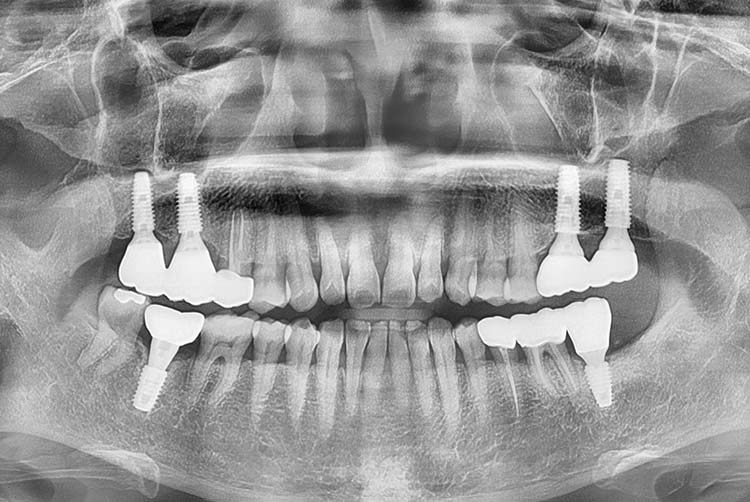

e962c42ada43c2f4aa37dd6d1f79d7df.jpg

치료후 : 2017-11-24